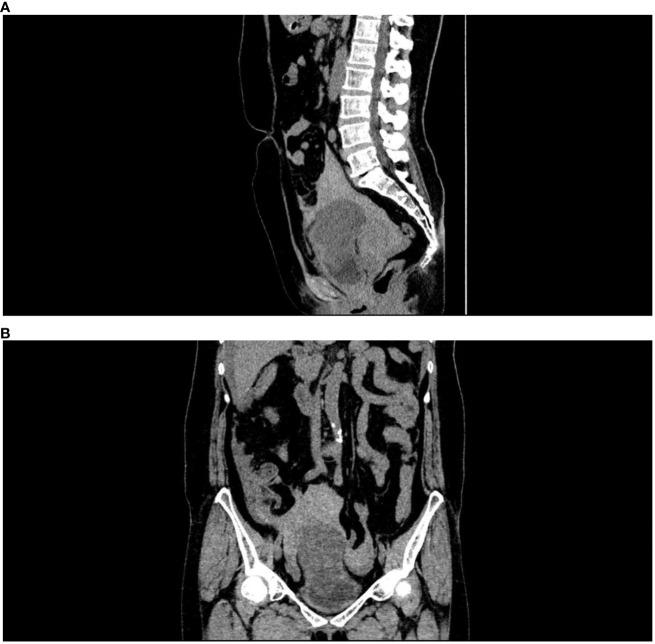

Acute abdomen caused by spontaneous rupture of the inflammatory myofibroblastic tumor of the urinary bladder (IMTUB) is a rare clinical emergency of the urinary system.It is difficult to distinguish it from spontaneous rupture of bladder caused by other causes before surgery. An emergency case of spontaneous rupture of IMTUB was reported. A 57-year-old middle-aged woman was admitted to the hospital because of "acute lower abdominal pain for 5 hours". No history of smoking and gross hematuria. The physical examination revealed visible abdominal tenderness as well as signs of shock. A pelvic CT scan shows a space-occupying lesion above the bladder with massive accumulation of blood. When the nature of the tumor could not be determined, emergency laparotomy and partial cystectomy were performed, and postoperative pathology confirmed cystitis myofibroblastic tumor. No local recurrence or distant metastasis of the tumor was observed during the regular follow-up period of 6 months. IMTUB should focus on prevention and treatment, with a combination of preoperative examination and postoperative pathology, and finally implement highly individualized treatment.

https://cdn.ncbi.nlm.nih.gov/pmc/blobs/3561/9706000/4347239fe98d/fonc-12-948263-g001.jpg